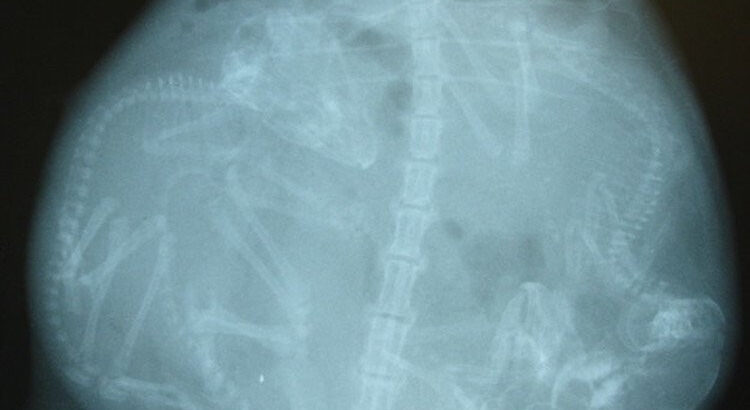

Le saviez-vous ? Les chauves-souris représentent un cinquième des mammifères et font partie du groupe le plus important après celui des rongeurs. Ces animaux vivent la nuit et sont souvent capables d'écholocation pour s'orienter dans le noir (pour repérer proies et obstacles).

Phénomène un peu surprenant, les femelles gardent en elles le sperme collecté jusqu’aux beaux jours. Quand les conditions idéales sont remplies (chaleur, nourriture abondante, tranquillité…), le sac à sperme s’ouvre et la fécondation peut avoir lieu. Les chauves-souris ne donnent naissance qu’à un seul petit (les cas de gémellité sont rares, sauf chez les pipistrelles). Les bébés naissent nus et aveugles. Les mamans accouchent la tête en bas et les bébés doivent s’accrocher sinon ils terminent leur course au sol…Les pères sont absents et les petits sont élevés dans des colonies maternelles.